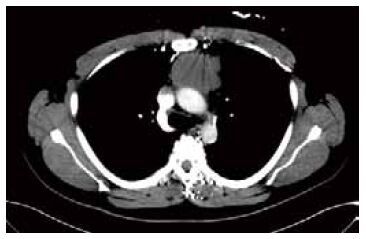

患者?男,30歲。因“顏面腫脹2周”于2014年7月23日入院,神志清楚,情緒穩定,精神差,活動后感氣緊。體格檢查:顏面部腫脹,頸靜脈怒張,雙上肢輕度腫脹。胸、腹部增強CT示:前縱隔團塊狀軟組織腫塊影,大小約 4.8 cm×5.8 cm,輪廓欠光整,密度欠均勻,增強后不均勻性強化,腫塊和升主動脈、主肺動脈干分界不清,頭臂干動脈周圍見軟組織影環繞,左頭臂靜脈被包埋或推移,該血管顯示不清,左胸壁多數側支血管開放,上腔靜脈及右頭臂靜脈見明顯受累征象(圖 1)。輔助檢查:血液常規、生物化學、凝血、輸血全套未見異常。心、肝、脾、胰、腎及腎上腺形態、結構未見異常。診斷結果:①縱隔腫瘤侵犯左右無名靜脈、左右鎖骨下靜脈及右頸內靜脈血栓形成;②上腔靜脈綜合征(SVCS)。

圖1

患者胸部增強掃描像